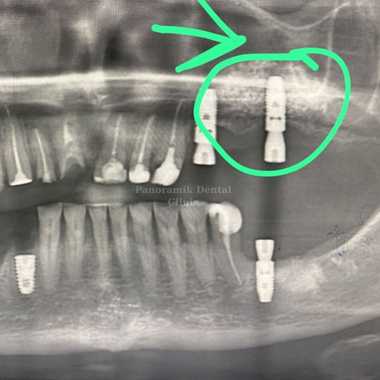

The sinus cavities perform the following functions: providing sound resonance, reducing pressure inside the skull, reducing the weight of the skull, as well as humidifying and warming the air. The sinus lift procedure is necessary due to sagging of the floor of the maxillary sinus adjacent to the upper molars and premolars.

This is a dental operation performed to increase the volume of bone tissue in the upper jaw. During implant treatment in case of insufficient bone tissue in the area of the upper molars and premolars, patients need to have  an operation called sinus lifting. There are two types of sinus lifting methods: open and closed.

Open (lateral) sinus lifting: It is a mini-surgical operation performed with local anesthesia in cases where the bone height is below 4 millimeters.

Closed (internal) sinus lifting: It is applied in cases where the bone height is between 4mm-7mm. The floor of the sinus is raised using a special instrument called an osteotome and filled with bone graft. This procedure is performed using local anesthesia. Sinus lifting operations are painless procedures that take 30-60 minutes. İf there is enough bone tissue, implants can be installed in the same session.